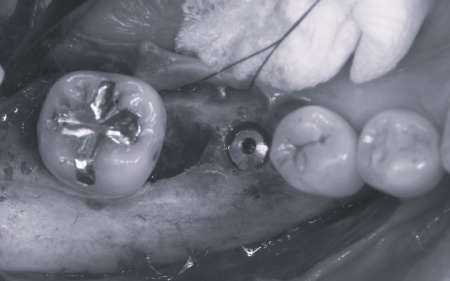

下左右の第1大臼歯を抜歯し、その部位にインプラントを埋め込む手術を行いました。同時に、インプラントの隣にある下の第2大臼歯に対して歯周組織再生療法を施しています。

さらにインプラントの周囲には角化歯肉移植を行いました。これは患者様のお口の中から歯ぐきを採取して移植する方法で、汚れが溜まりにくく清掃しやすい歯ぐきの状態をつくります。

診断結果を踏まえ、まず下左右の第1大臼歯については抜歯したあとにインプラントで補う方法を提案しました。

インプラント治療は、周囲の歯を削ることなく失った歯の部分のみを単独で補うことができます。

ただし、外科手術が必要となり治療期間が比較的長くなる点がデメリットです。